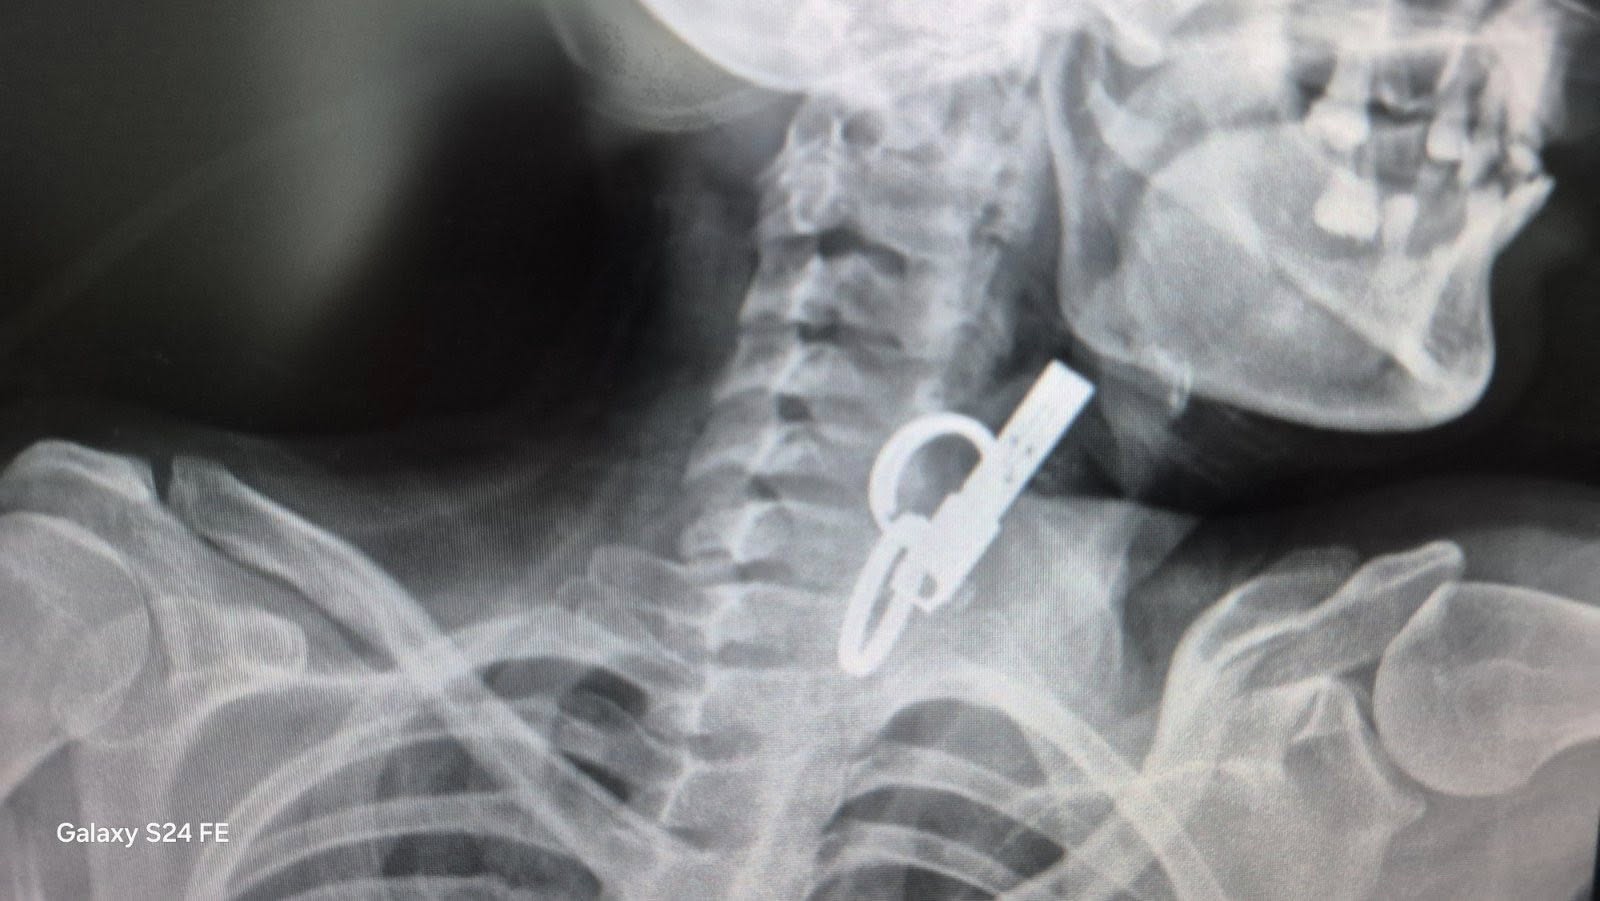

У Гусятині лікарі витягли зі стравоходу жінки ключ від дверей

— Завдяки наявності сучасного ендоскопічного обладнання та злагодженій роботі команди фахівців у закладі успішно проведено ендоскопічне видалення великого стороннього тіла зі стравоходу без виконання хірургічного розрізу, — йдеться в повідомленні.

Також видання Вікна-новини пише, що 40-річна пацієнтка близько тижня жила з ключем у стравоході — вона проковтнула його, щоб родичі не змогли потрапити до її помешкання.

— Жінку доправили до лікарні у важкому стані, тож рішення про операцію ухвалювали терміново. Після втручання їй встановили гастростому для відновлення стравоходу. Наразі стан пацієнтки стабільний, зазначили журналісти.